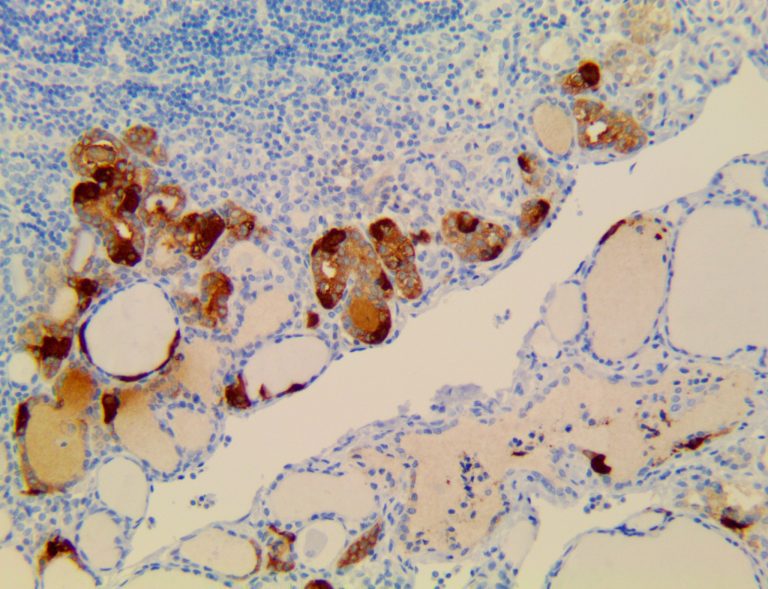

Clinical and laboratory manifestations of HLH include fever, enlarged liver and/or spleen, neurologic dysfunction, coagulopathy, liver dysfunction, cytopenias (i.e., low levels of erythrocytes, leukocytes, and/or platelets), hypertriglyceridemia, hyperferritinemia, hemophagocytosis, and eventually diminished NK cell activity as the immune system becomes progressively paralyzed. HLH can be familial (primary HLH) or secondary to another disease process (sHLH), such as rheumatic disease, in which it is referred to as macrophage activation syndrome (MAS, characterized by elevated ferritin).

This activation induces inflammatory monocytes to highly express IL-6, starting a localized and then systemic cascade effect that results in hyperproduction of IL-6, which accelerates the inflammatory process. Because IL-6 also increases vascular permeability, excessive levels cause blood vessels to become very leaky. This, along with clotting factors released from vascular endothelial cells, stimulates the coagulation cascade, resulting in microthrombosis (tiny clots), which leads to ischemia and tissue death of the kidney, intestines, heart, liver, brain and extremities.